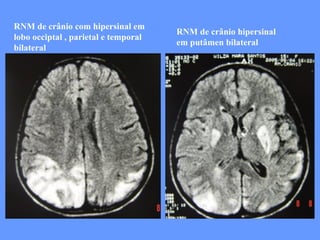

RNM de crânio com hipersinal em lobo occiptal , parietal e temporal bilateral RNM de crânio hipersinal em putâmen bilateral

Histórico anterior e familiar: ND normal. Aos 9 anos episódio de perda da visão bilateral com regressão após 3 meses. Aos 11 anos cefaléia pulsátil com náusea . Aos 13 anos início de crise convulsiva generalizada. Hà 6 meses início agudo de coma com hemiparesia à esquerda precedido de perda da audição e crise convulsiva com duração de 3 dias levando seqüela cognitiva e motora.  Há 50 dias início agudo de hemianopsia à direita.  Avó falecida de cardiopatia e diabetes e mãe com migrânea.

RNM de crâniocom hipersinal em lobo occiptal , parietal e temporal bilateral RNM de crânio hipersinal em putâmen bilateral